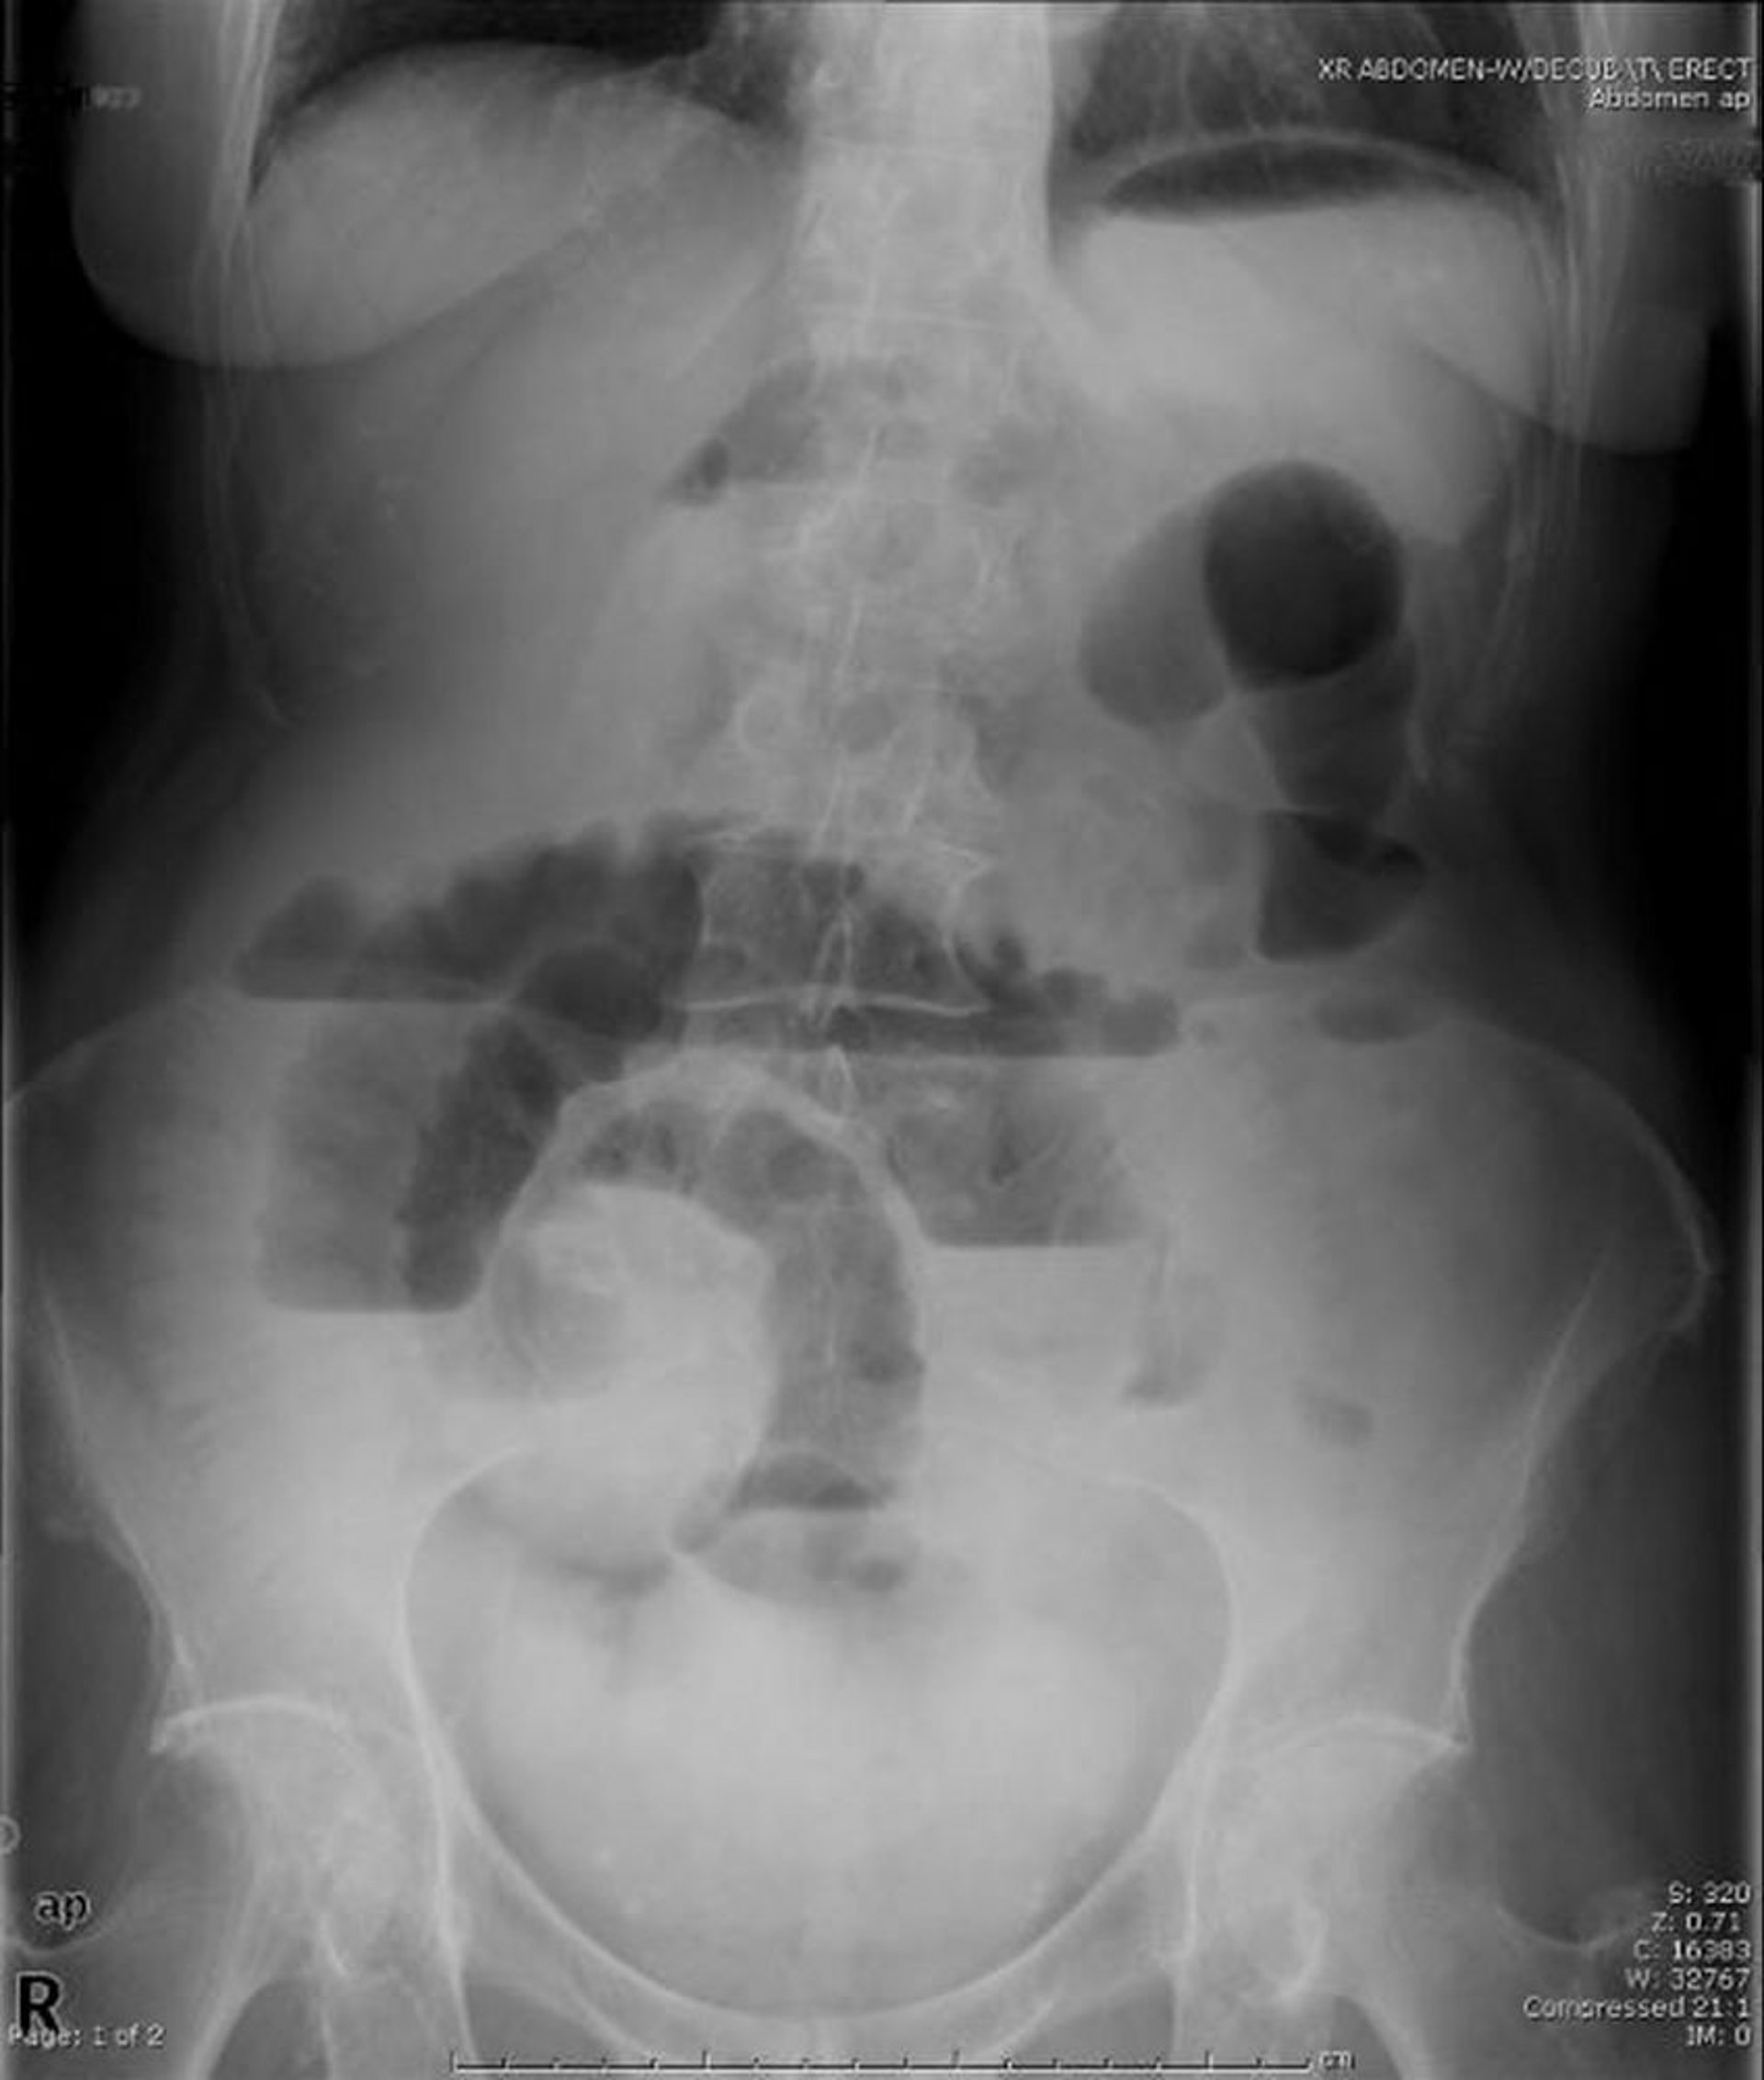

Obstrucción del intestino delgado (radiografía de pie)

Esta radiografía abdominal con el paciente de pie en la que se observa obstrucción del intestino delgado. Tenga en cuenta los múltiples niveles de aire-líquido.

Image provided by Parswa Ansari, MD.